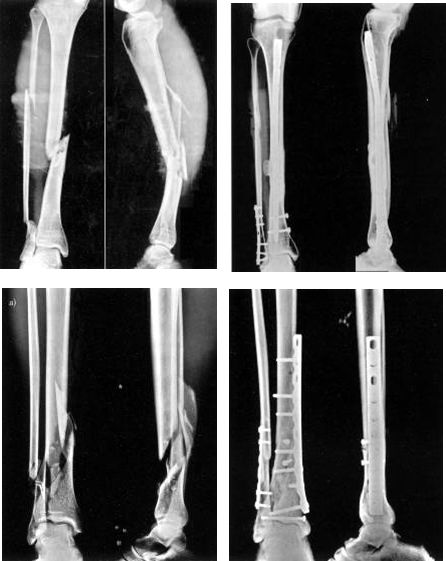

La réduction précoce et la fixation interne sont privilégiées pour les fractures ouvertes et fermées, en particulier pour celles compliquées de lésions vasculaires, nerveuses ou tendineuses, la chirurgie doit être effectuée immédiatement.

Déterminer la nature de la violence liée aux blessures

Les blessures à haute énergie sont souvent accompagnées de lésions graves des tissus mous.Elle se caractérise par un gonflement des membres, des cloques, une abrasion cutanée et une lacération cutanée.L'opération doit être reportée pour le moment.Dans le même temps, le syndrome de l'espace fascial et les lésions vasculaires et nerveuses doivent être exclus.

La particularité de l'anatomie - l'importance de la couverture des tissus mous.

Stade précoce : dans les 8h

Le fixateur externe est considéré comme le premier choix pour un traitement précoce.

Support de gypse

Traction calcanéenne

Phase II : environ 2 semaines.

Il n'y avait pas d'infection systémique évidente ni de traumatisme aigu.

Pas de gonflement ni d'exsudation de la plaie.

L'ampoule est sèche, le gonflement diminue et les marqueurs osseux peuvent être touchés.

Peau ridée, des lignes de peau apparaissent.

Le résultat du traitement de la fracture de Pilon dépend de la qualité de la reconstruction articulaire et de l'état de la couverture des tissus mous.

Le meilleur moment pour la chirurgie dépend de l'état des tissus mous :

Stade précoce : l'opération a été réalisée en 6 ~ 8h, qui a duré 2 ~ 3h.

Délai : 7 ~ 10 jours, le gonflement a disparu et les rides de la peau sont apparues.

Quatre principes traditionnels qui doivent être suivis dans la reconstruction chirurgicale en un temps :

Reconstruction du péroné

Reconstruction de la surface articulaire tibiale

Greffe osseuse

Support de plaque osseuse